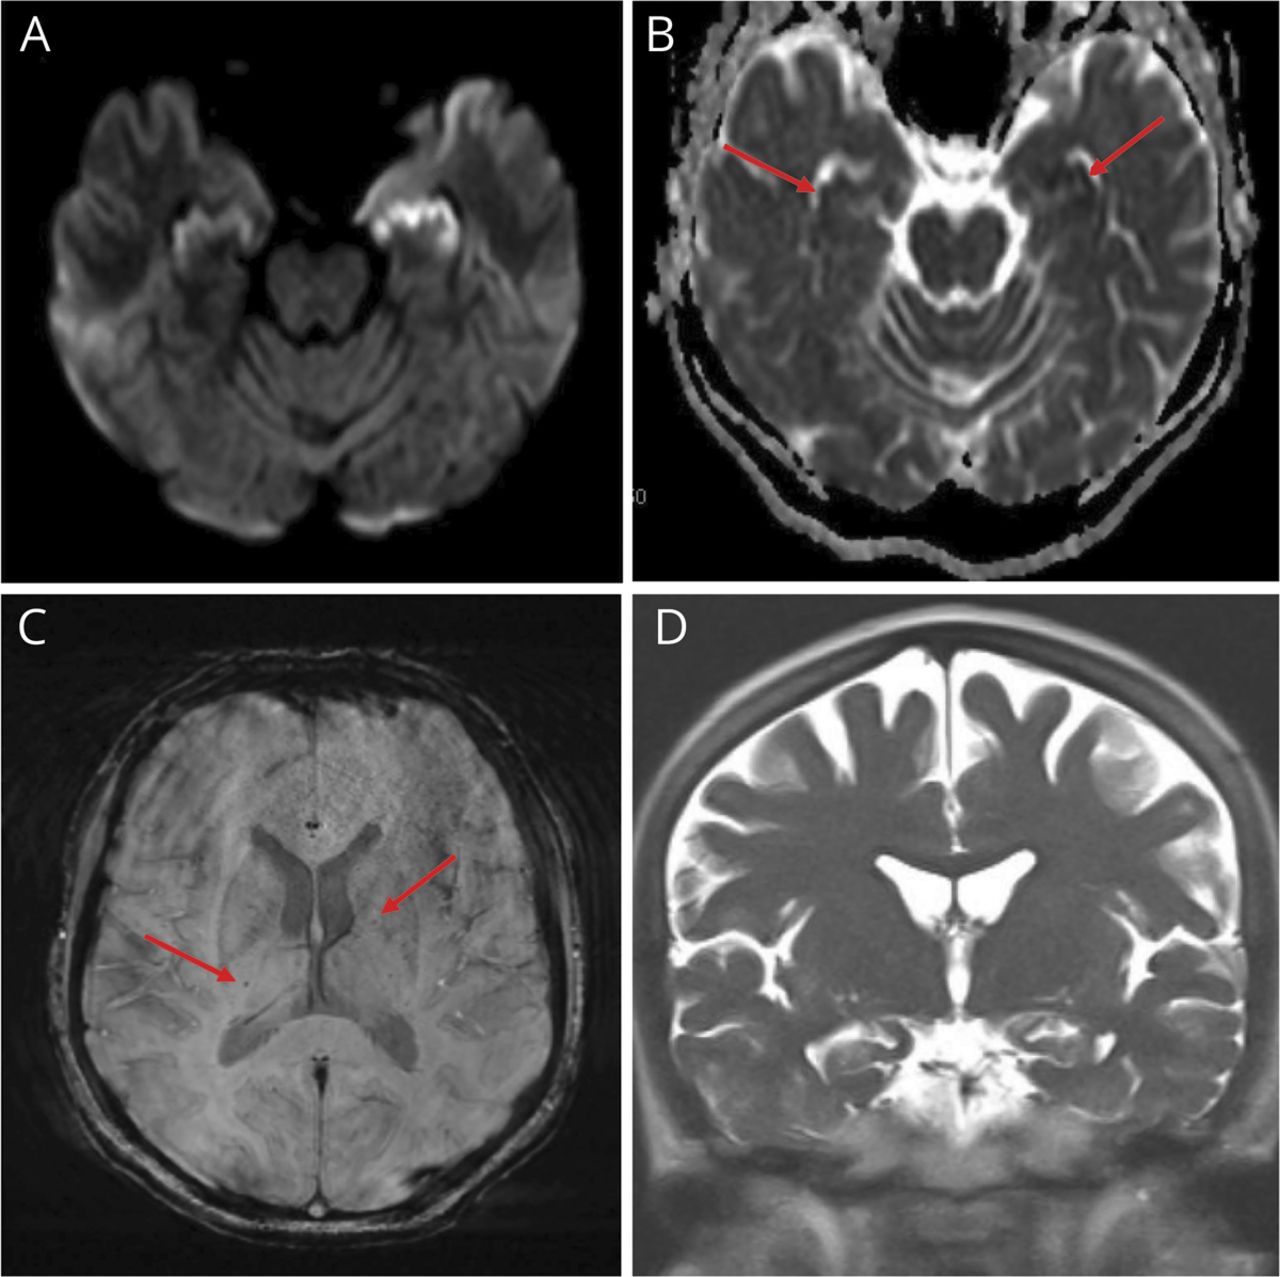

一位39岁的女性出现发热、不适,头痛在访问坦桑尼亚。外围涂片显示恶性疟原虫和疟原虫那寄生虫血症> 14%。几小时内,她变得反应迟钝。MRI显示点状的疫源地的microhemorrhage深层白质和海马限制扩散(图)。五天的video-EEG负发作。她在3周后出院奎尼丁,强力霉素和伯氨喹。重复MRI显示双边海马硬化;重复脑电图是正常的。随访检查只是显著的短期记忆障碍。

图

在脑型疟疾MRI扫描

大脑MRI与积极diffusion-weighted成像(A)和(B)表观扩散系数辍学(箭头)符合急性缺血。(C) Susceptibility-weighted成像显示小面积的microhemorrhage深白质(箭头)。(D)随访MRI 2个月后展示了双边海马硬化。

microhemorrhages和缺血脑型疟疾。1白质弥漫性水肿和T2 hyperintensities也常见,2虽然不是欣赏。鉴于长期的脑电图监测没有发作,两国微血管缺血海马硬化可能是次要的。